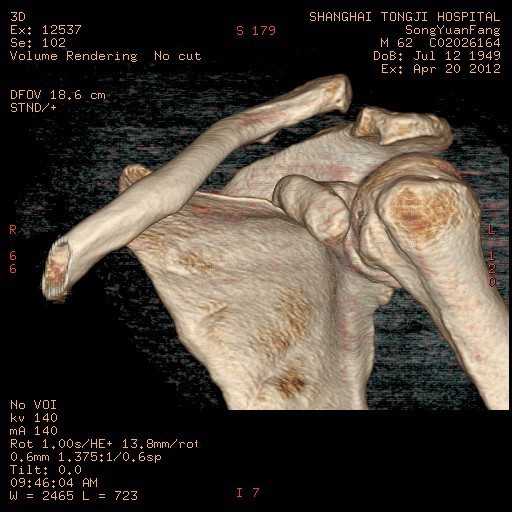

主诉:摔伤后左肩疼痛伴活动受限20天。 病史:患者入院前20天不慎摔伤,左肩不能活动,遂来我院急诊,摄片示左肩锁关节脱位,入院治疗。

完善术前检查和准备后,行左肩锁关节脱位切开复位内固定术,术顺,术后安返病房,内固定使用锁骨钩。